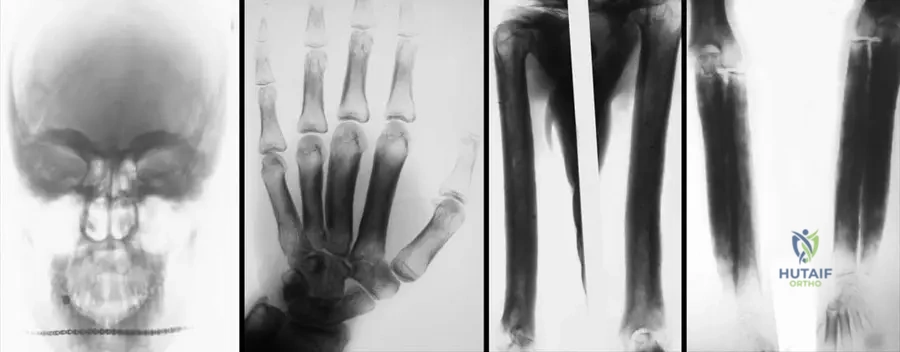

Rationale: The teaching case explicitly states that Progressive Diaphyseal Dysplasia "is an autosomal dominant disorder involving the diaphyses of the long bones, skull base, and clavicles." The radiographic images (Fig. 1.120) also clearly show cortical thickening and sclerosis in the diaphyses. Therefore, the diaphyses (D) are the primary affected part of the long bones.

Rationale: Fig. 1.122 a–d shows "Definitive, late form of progressive diaphyseal dysplasia on anteroposterior radiographs of skull (a), hand (b), arm (c), forearm (d)". The image specifically includes a radiograph of the hand (b), demonstrating involvement of the metacarpals and phalanges. The other options are not explicitly shown or mentioned as affected in the provided images/text.

Rationale: Fig. 1.120 a–c is captioned: "Diaphyseal cortical thickening and sclerosis of long tubular bones are the main characteristics of Camurati-Engelmann disease." The images clearly illustrate this feature in the humerus, femur, tibia, and fibula. Options A, B, D, and E describe features not seen in the provided images or characteristic of this disease.